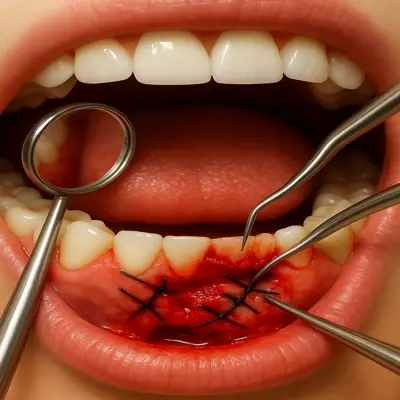

جراحی دندان معمولاً با بیحسی موضعی انجام میشود؛ پزشک ابتدا لثه را بیحس میکند و با عکس رادیوگرافی مسیر ریشه/دندان را دقیق مشخص میکند.

سپس در صورت نیاز یک برش کوچک روی لثه میزند، دندان یا ریشه را (گاهی به چند قسمت) خارج میکند و محل را شستوشو و تمیز میکند.

در پایان، در صورت لزوم بخیه و گاز استریل گذاشته میشود و دستور دارو، کمپرس و مراقبتهای چند روز اول داده میشود.

نمای جراحی لثه و خارجسازی دندان عفونی با ابزار دندانپزشکی

جراحی لثه معمولاً زمانی انجام میشود که عفونت یا التهاب پیشرفته باعث آسیب به بافت نگهدارندهی دندان شده باشد. هدف، حذف بافتهای عفونی، پاکسازی عمق لثه و بازسازی بافت سالم است.

این جراحی با بیحسی انجام میشود و با بخیههای ظریف بسته میشود تا فرآیند ترمیم بهخوبی پیش برود. رعایت مراقبتهای پس از عمل مانند استفاده از دهانشویه و پرهیز از غذاهای سفت، روند بهبودی را تسریع میکند.

ایجاد برش در لثه:

جراح دهان با استفاده از ابزار ظریف، برشی کوچک روی لثه ایجاد میکند تا به دندان یا بافت آسیبدیده دسترسی پیدا کند. این مرحله باید با دقت بالا انجام شود تا خونریزی لثه به حداقل برسد. -

بخیه و پانسمان:

پس از پایان جراحی، محل برش بخیه میشود تا روند ترمیم سریعتر انجام گیرد. پانسمان مخصوص برای جلوگیری از خونریزی و محافظت از ناحیه جراحی روی لثه قرار داده میشود. -